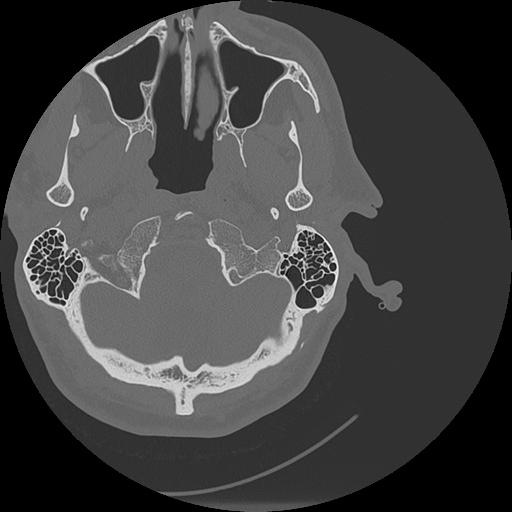

7 HUESO,,Vol,0.5,HUESO,,